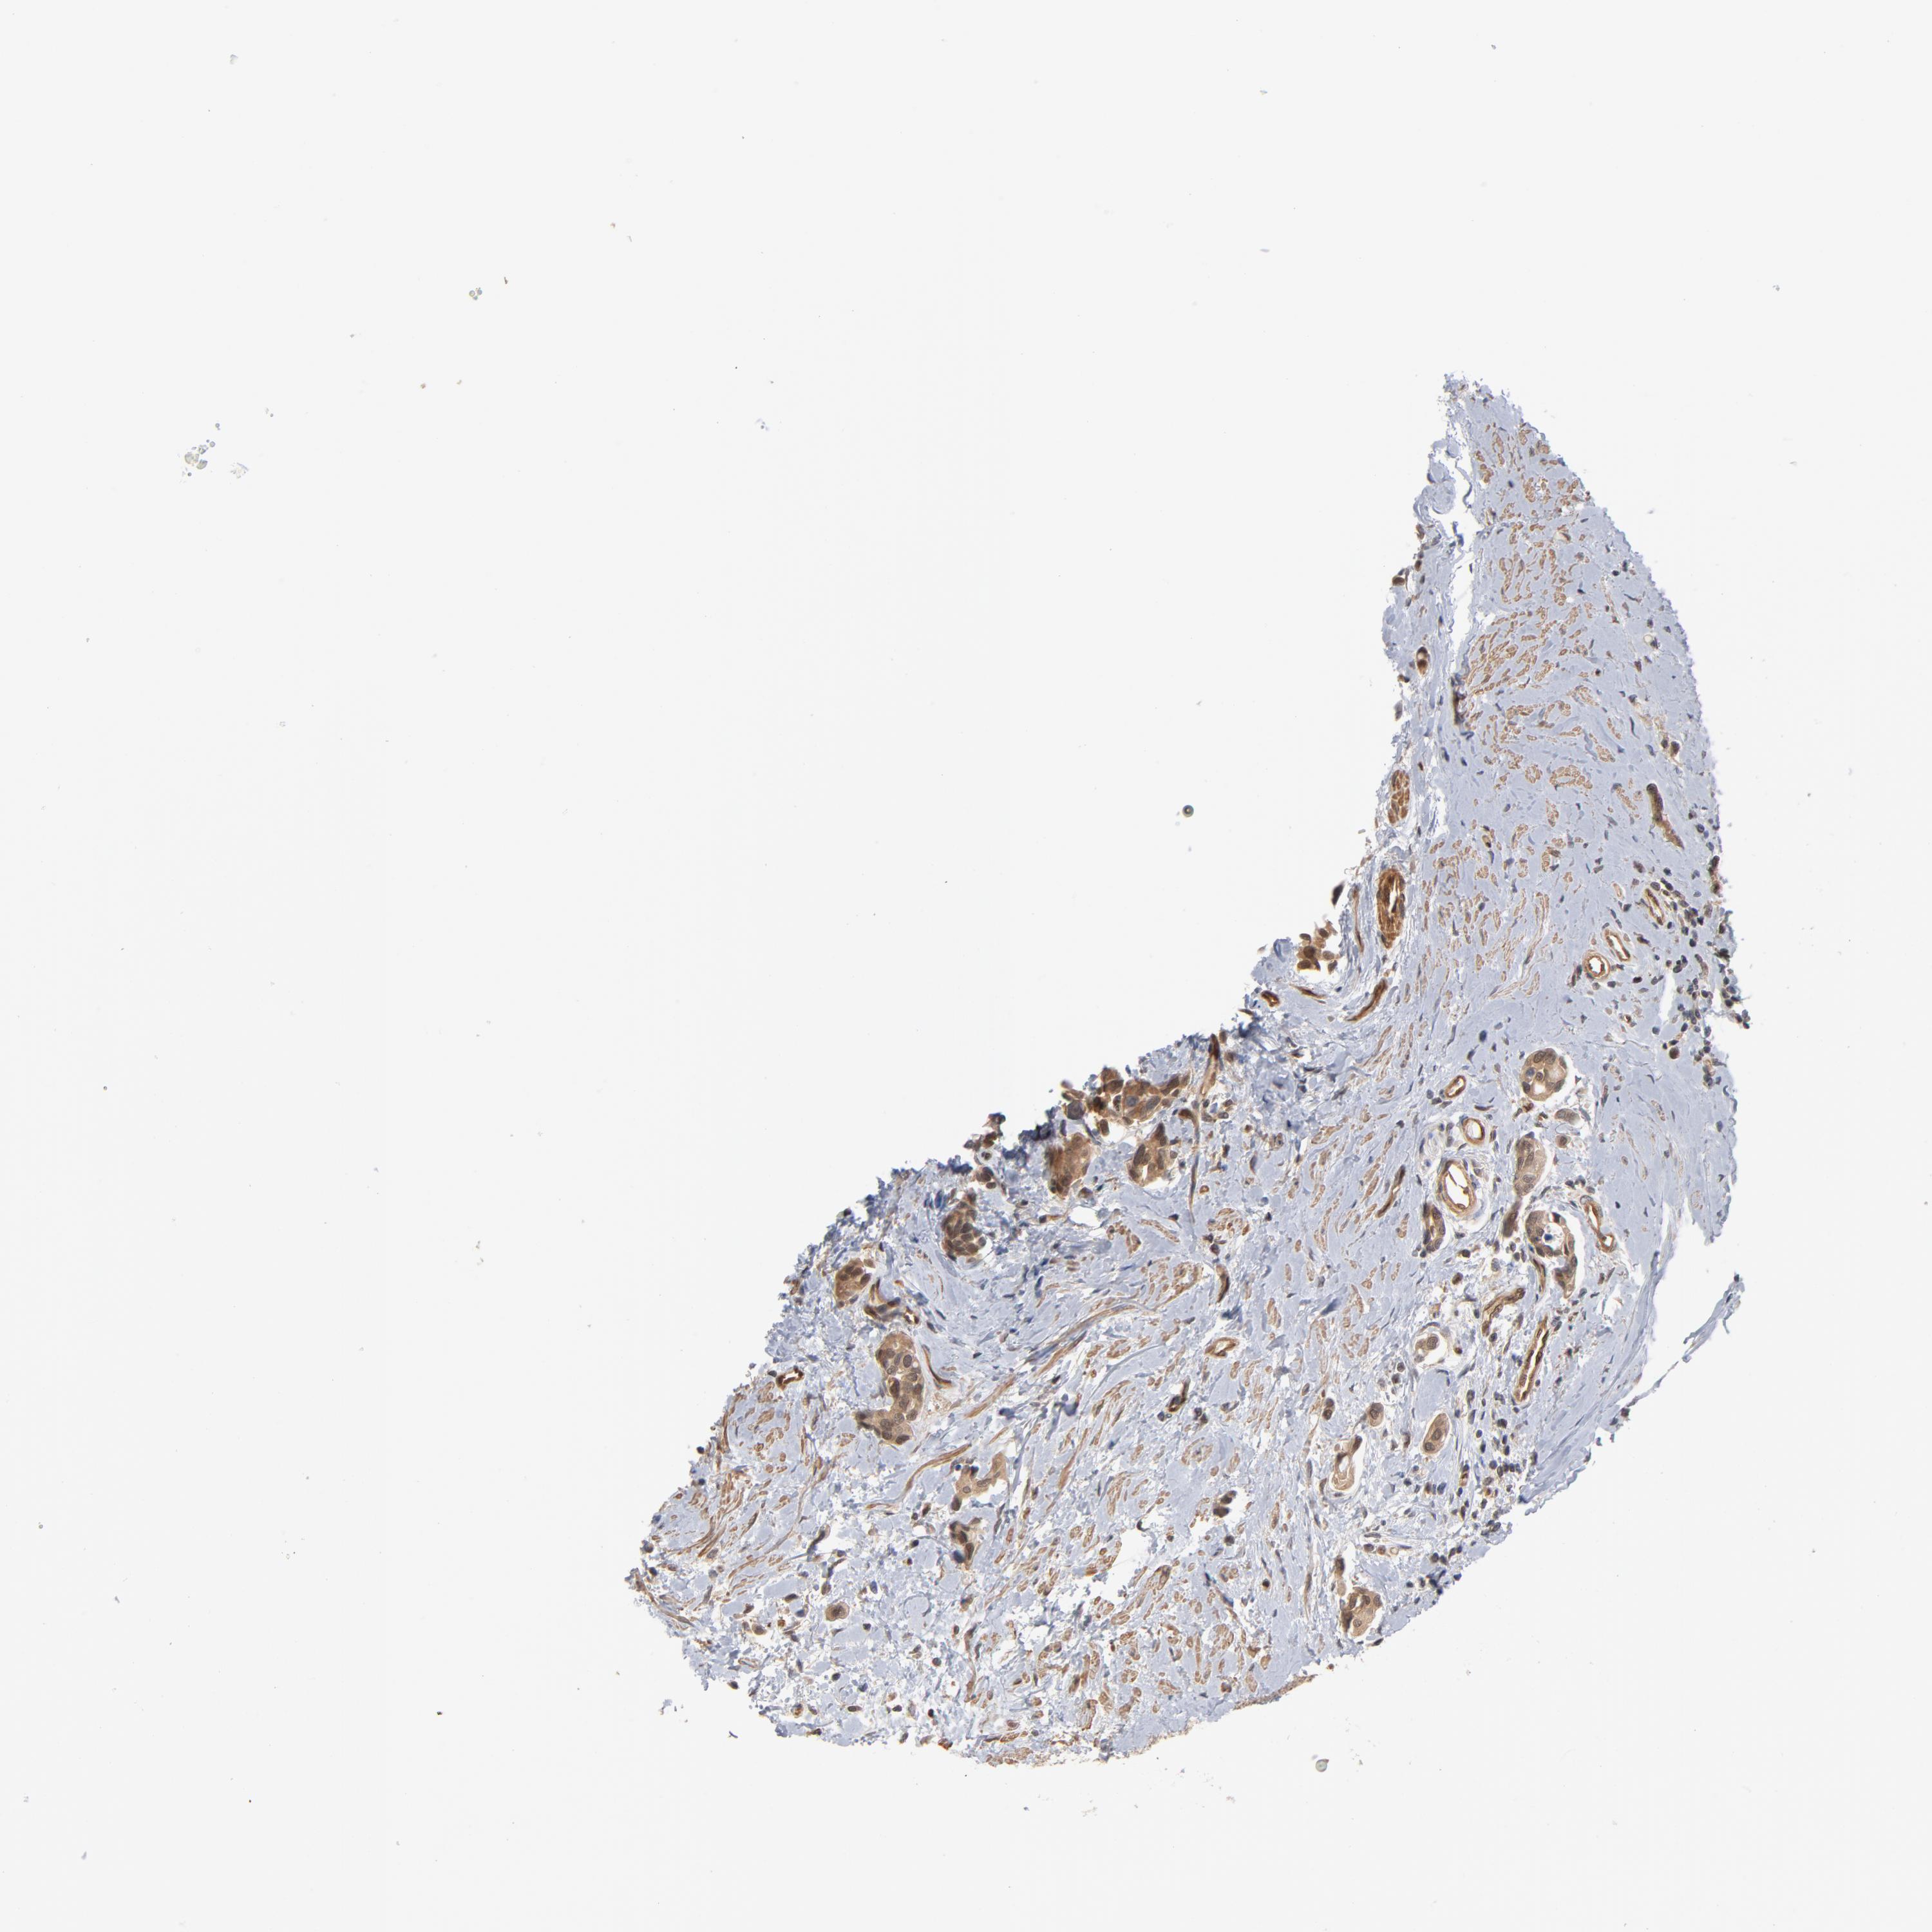

UROTHELIAL CANCER - Protein expressioni

A mouse-over function shows sample information and annotation data. Click on an image to view it in a full screen mode. Samples can be filtered based on level of antibody staining by selecting one or several of the following categories: high, medium, low and not detected. The assay and annotation is described here.

Note that samples used for immunohistochemistry by the Human Protein Atlas do not correspond to samples in the TCGA dataset.

Antibody stainingi

Antibody staining in the annotated cell types in the current human tissue is reported as not detected, low, medium, or high, based on conventional immunohistochemistry profiling in selected tissues. This score is based on the combination of the staining intensity and fraction of stained cells.

Each image is clickable and will lead to virtual microscopy that enables deeper exploration of all samples and also displays staining intensity scores, fraction scores and subcellular localization as well as patient and tissue information for each sample.

Antibody HPA003928

Antibody CAB004214

Staining

High

Medium

Low

Not detected

Intensity

Strong

Moderate

Weak

Negative

Quantity

>75%

75%-25%

<25%

None

Location

Nuclear

Cytoplasmic/membranous

Cytoplasmic/membranous,nuclear

Urothelial carcinoma, High grade

Urothelial carcinoma, Low grade